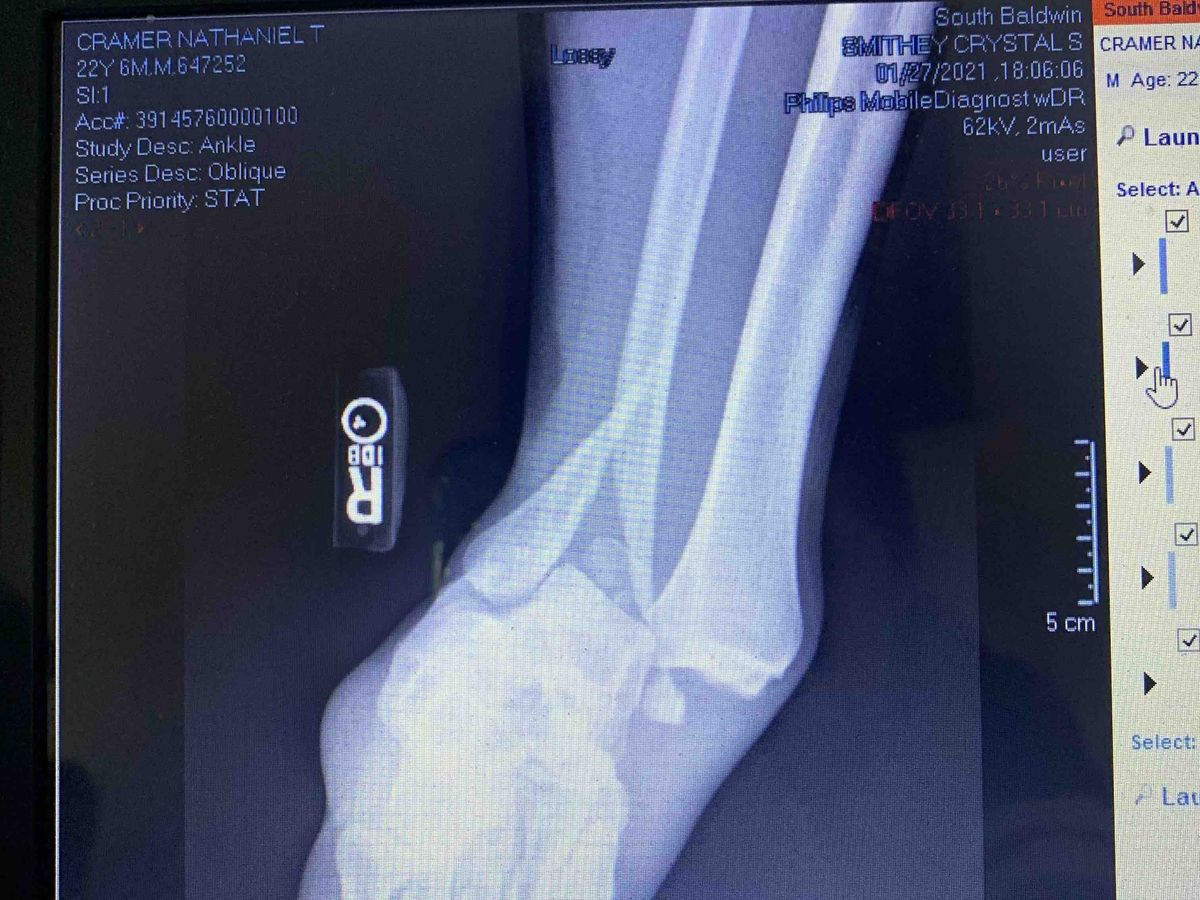

We are raising money to help with Nate’s surgery. He shattered his ankle in three different places and is in horrible amounts of pain. Anything helps.